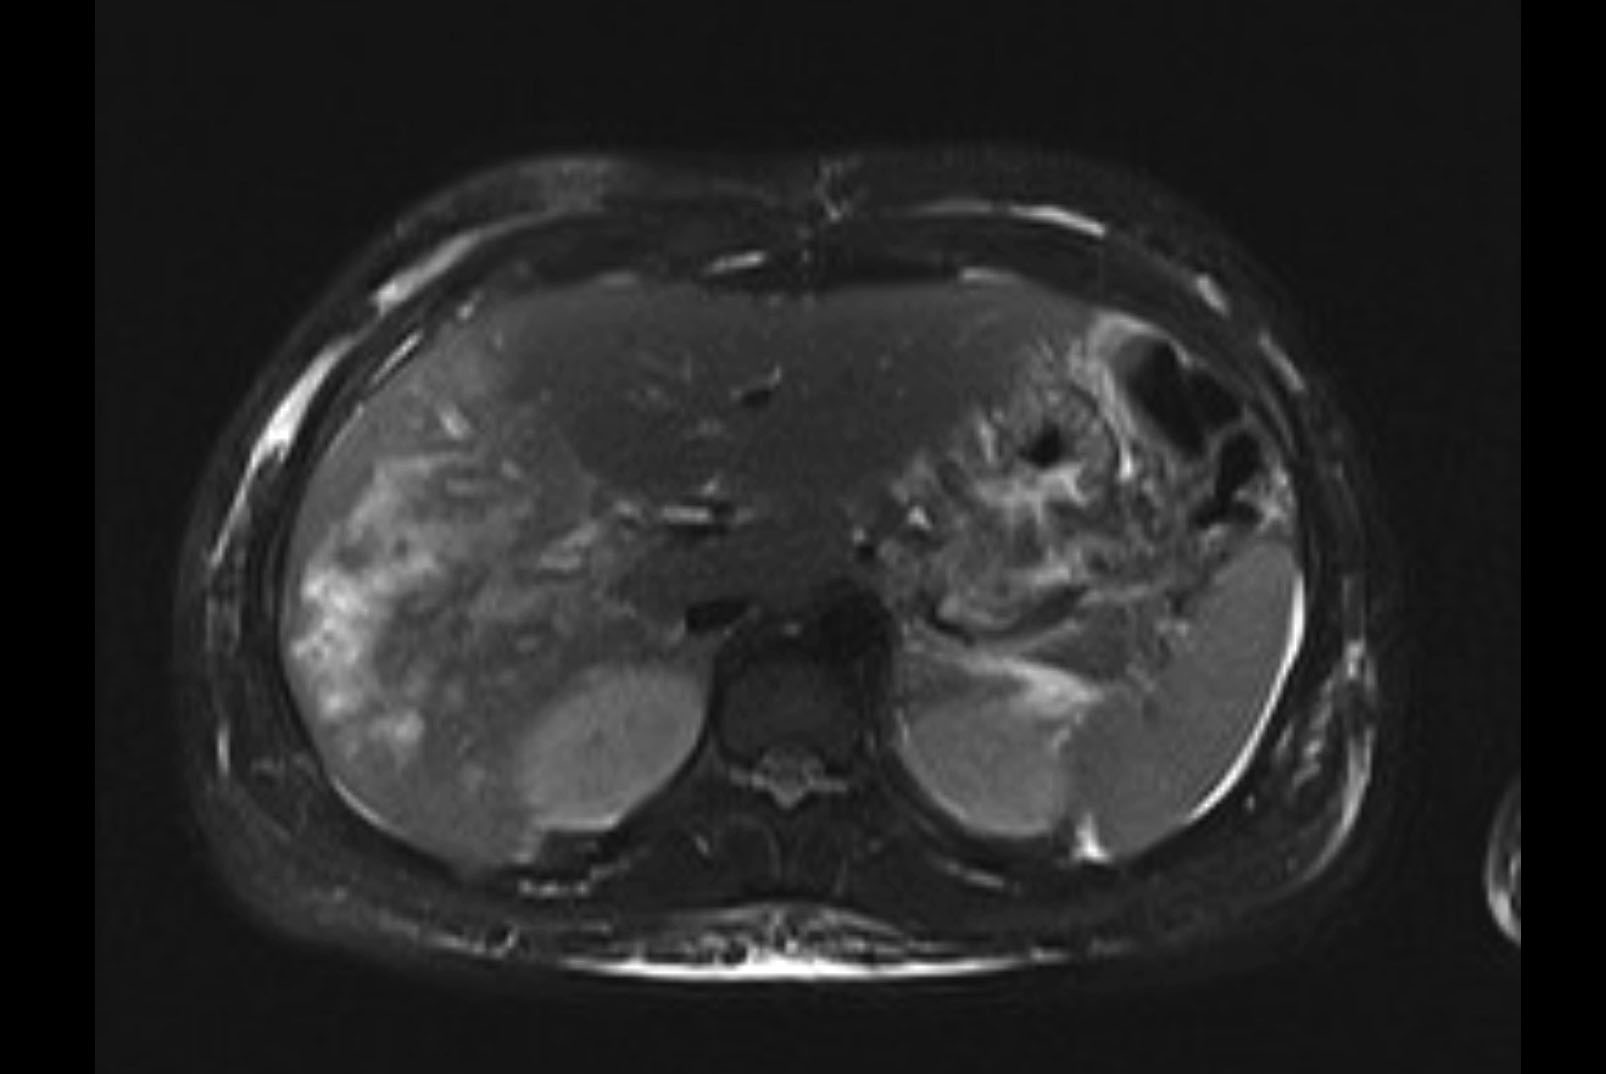

Imaging Analysis

Look through the patient's CT scan to identify any areas of concern for the necessary procedure.

MRI T2

Based on initial findings, which issue(s) would you be most concerned about?